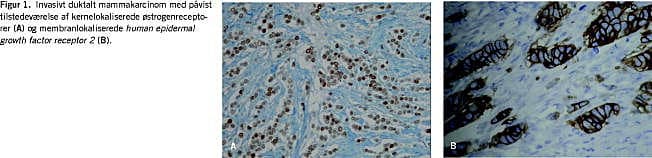

Tilstedeværelsen af østrogen- og progesteronreceptor påvises immunhistokemisk (Figur 1A ). Ca. 80% af alle mammakarcinomer er receptorpositive [7]. Tilstedeværelsen af receptorerne er knyttet til andre, prognostisk favorable faktorer som lav malignitetsgrad og negativ lymfeknudestatus, ligesom andelen af receptorpositive tumorer er stigende med stigende alder. Hormonreceptorerne (HR) er karakteriseret ved deres prædiktive værdi, idet ca. 60% af de HR-positive patienter har effekt af antiøstrogenbehandling.

Human epidermal growth factor receptor 2 - HER2

I 20-25% af brystkræfttilfældene ses overekspression af overfladereceptoren human epidermal growth factor receptor 2 (HER2), sædvanligvis betinget af amplifikation af genet, som koder for dannelsen af proteinet. HER2-positivitet undersøges verden over standardiseret med en blanding af immunhistokemi (IHC) (Figur 1B ) og fluorescens in situ-hybridisering (FISH). Overekspression/amplifikation af protein og/eller gen, regn es normalt for at være en selvstændig prognostisk faktor for recidiv og død. I en gennemgang af publicerede oversigtsartikler [8] konkluderes det, at HER2 med overbevisende evidens er en prognostisk markør hos lymfeknudepositive patienter og en mindre overbevisende markør hos lymfeknudenegative patienter, samt at der i flere af undersøgelserne med lang opfølgningstid var en tidsafhængighed, hvor betydningen af HER2-positivitet efterhånden forsvandt. Kun gennem en metaanalyse vil man endeligt kunne afklare HER2's betydning som prognostisk faktor.